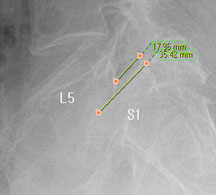

즉, 척추전방위증은 통증을 일으키는 원인질환(디스크, 협착증)을 치료하는 것이 척추 뼈를 더 이상 앞으로 밀려나가지 않게 하는 치료라고 볼 수 있습니다. 모커리는 뼈가 50% 이상 밀려나간 2단계의 척추전방위증도 비수술로 치료하고 있으며, 이러한 한방치료 효과를 객관적으로 검증하여 유명학회 및 논문에 계속해서 발표하고 있습니다.

모커리한방병원은 50% 정도 밀려나간 2단계의 척추전방위증 환자를 대상으로 약 3주간의 입원집중치료를 실시한 결과, 입원 시보다 80% 이상 통증이 감소되어 치료되었습니다. 통증 없이 걷는 시간도 약 3배 정도 증가되어 단기간에 수술 없이 높은 치료효과가 나타났다는 것을 대한침구의학회에 발표하였습니다. 50% 정도 밀려나간 2단계의 중증 척추전방전위증 환자이면서 심한 척추협착증 증상을 나타내는 환자를 치료한 결과입니다.